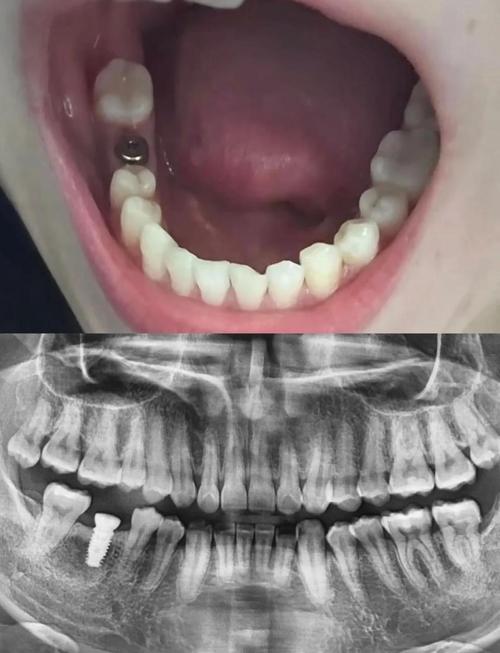

- 骨密度与骨量检测:采用双能X线吸收法(DXA)检测腰椎或髋部骨密度,明确骨质疏松程度(T值≥-1.0SD为正常,-1.0~-2.5SD为骨量减少,≤-2.5SD为骨质疏松);通过锥形束CT(CBCT)评估牙槽骨的骨量(高度、宽度)及骨密度(可通过Hounsfield值定量分析,骨密度值越低,骨质量越差)。